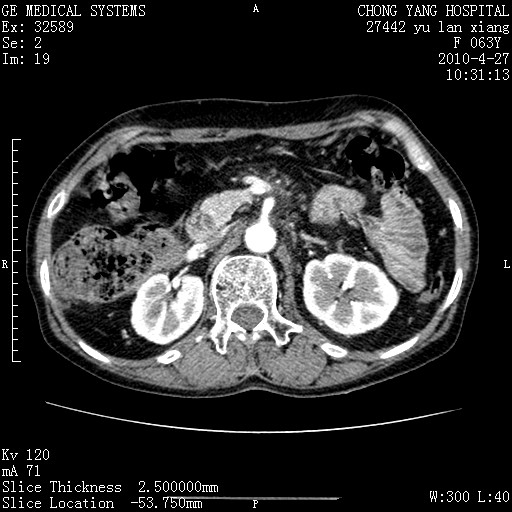

标题: CT26066:F63Y 上腹正中压痛半月,CA199:7400u/ml,MR示胰腺炎伴 [打印本页]

胰腺癌侵犯腹腔动脉干-分支、胃壁、左侧膈肌伴胰周及腹膜后淋巴结转移、胆囊切除术后。

胰腺癌侵犯腹腔动脉干-分支、胃壁、左侧膈肌伴胰周及腹膜后淋巴结转移、胆囊未显影。